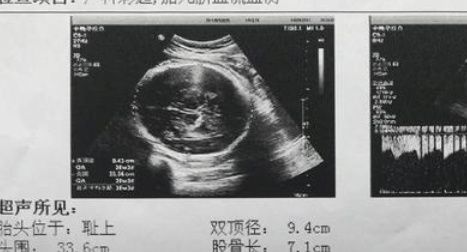

在做产检的时候,最后都会有一个产检单,有一项数据就是宝宝双顶径的数据,其实双顶径是判断宝宝性别非常重要的一个信号,如果说看到双顶径的数据和股骨的长度相差值大于两厘米的话,很有可能怀的就是一位小公子,其实这个数字可能会随着妈妈怀孕时间的不断增长而会发生一些变化,在怀孕早期的时候数字可能相对来说会比较小,所以说最好是可以在孕中期或者是孕晚期的时候再来做一次检查,这个时候可能得出的数据就会比较准确。